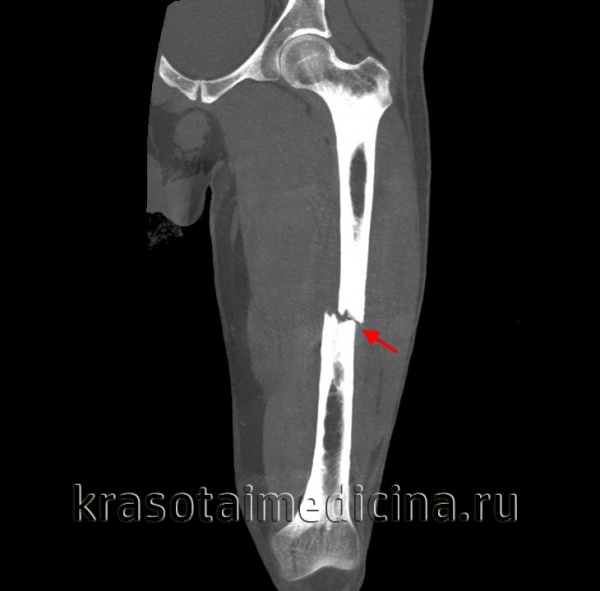

Подвертельные переломы бедра

Подвертельными считают переломы, располагающиеся на расстоянии до 5 см дистальнее малого вертела. Эти переломы обычны у больных молодого возраста и часто являются следствием воздействия значительной повреждающей силы. Переломы могут быть спиральными, оскольчатыми, смещенными или представлять собой как бы продолжение межвертельного перелома. Большинство ортопедов пользуются классификацией Fieldings.

Наиболее типичным механизмом повреждения является падение с комбинированным действием прямой и ротационной сил.

У больного отмечают боль и припухлость в области тазобедренного сустава и верхнего отдела бедра. Кроме того, вследствие воздействия значительной силы, вызвавшей этот перелом, возможны повреждения нижней конечности или коленного сустава на стороне повреждения.

Лечение подвертельных переломов бедра

Неотложная помощь при этих переломах включает иммобилизацию шиной Sager, лед, анальгетики, внутривенное введение жидкости для коррекции гиповолемии и госпитализацию для открытой репозиции с внутренней фиксацией. Переломы со значительной фрагментацией лучше лечить скелетным вытяжением.